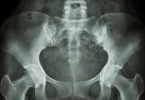

• 骨盆骨折最危险有什么并发症

骨盆骨折最危险有什么并发症

骨盆骨折最危险的并发症主要有失血性休克、脂肪栓塞综合征、深静脉血栓形成、多器官功能障碍综合征、感染等。骨盆骨折多由高能量创伤引起,可能伴随剧烈疼痛、活动受限等症状,需紧急就医处理。1、失血性休克骨盆骨 ...